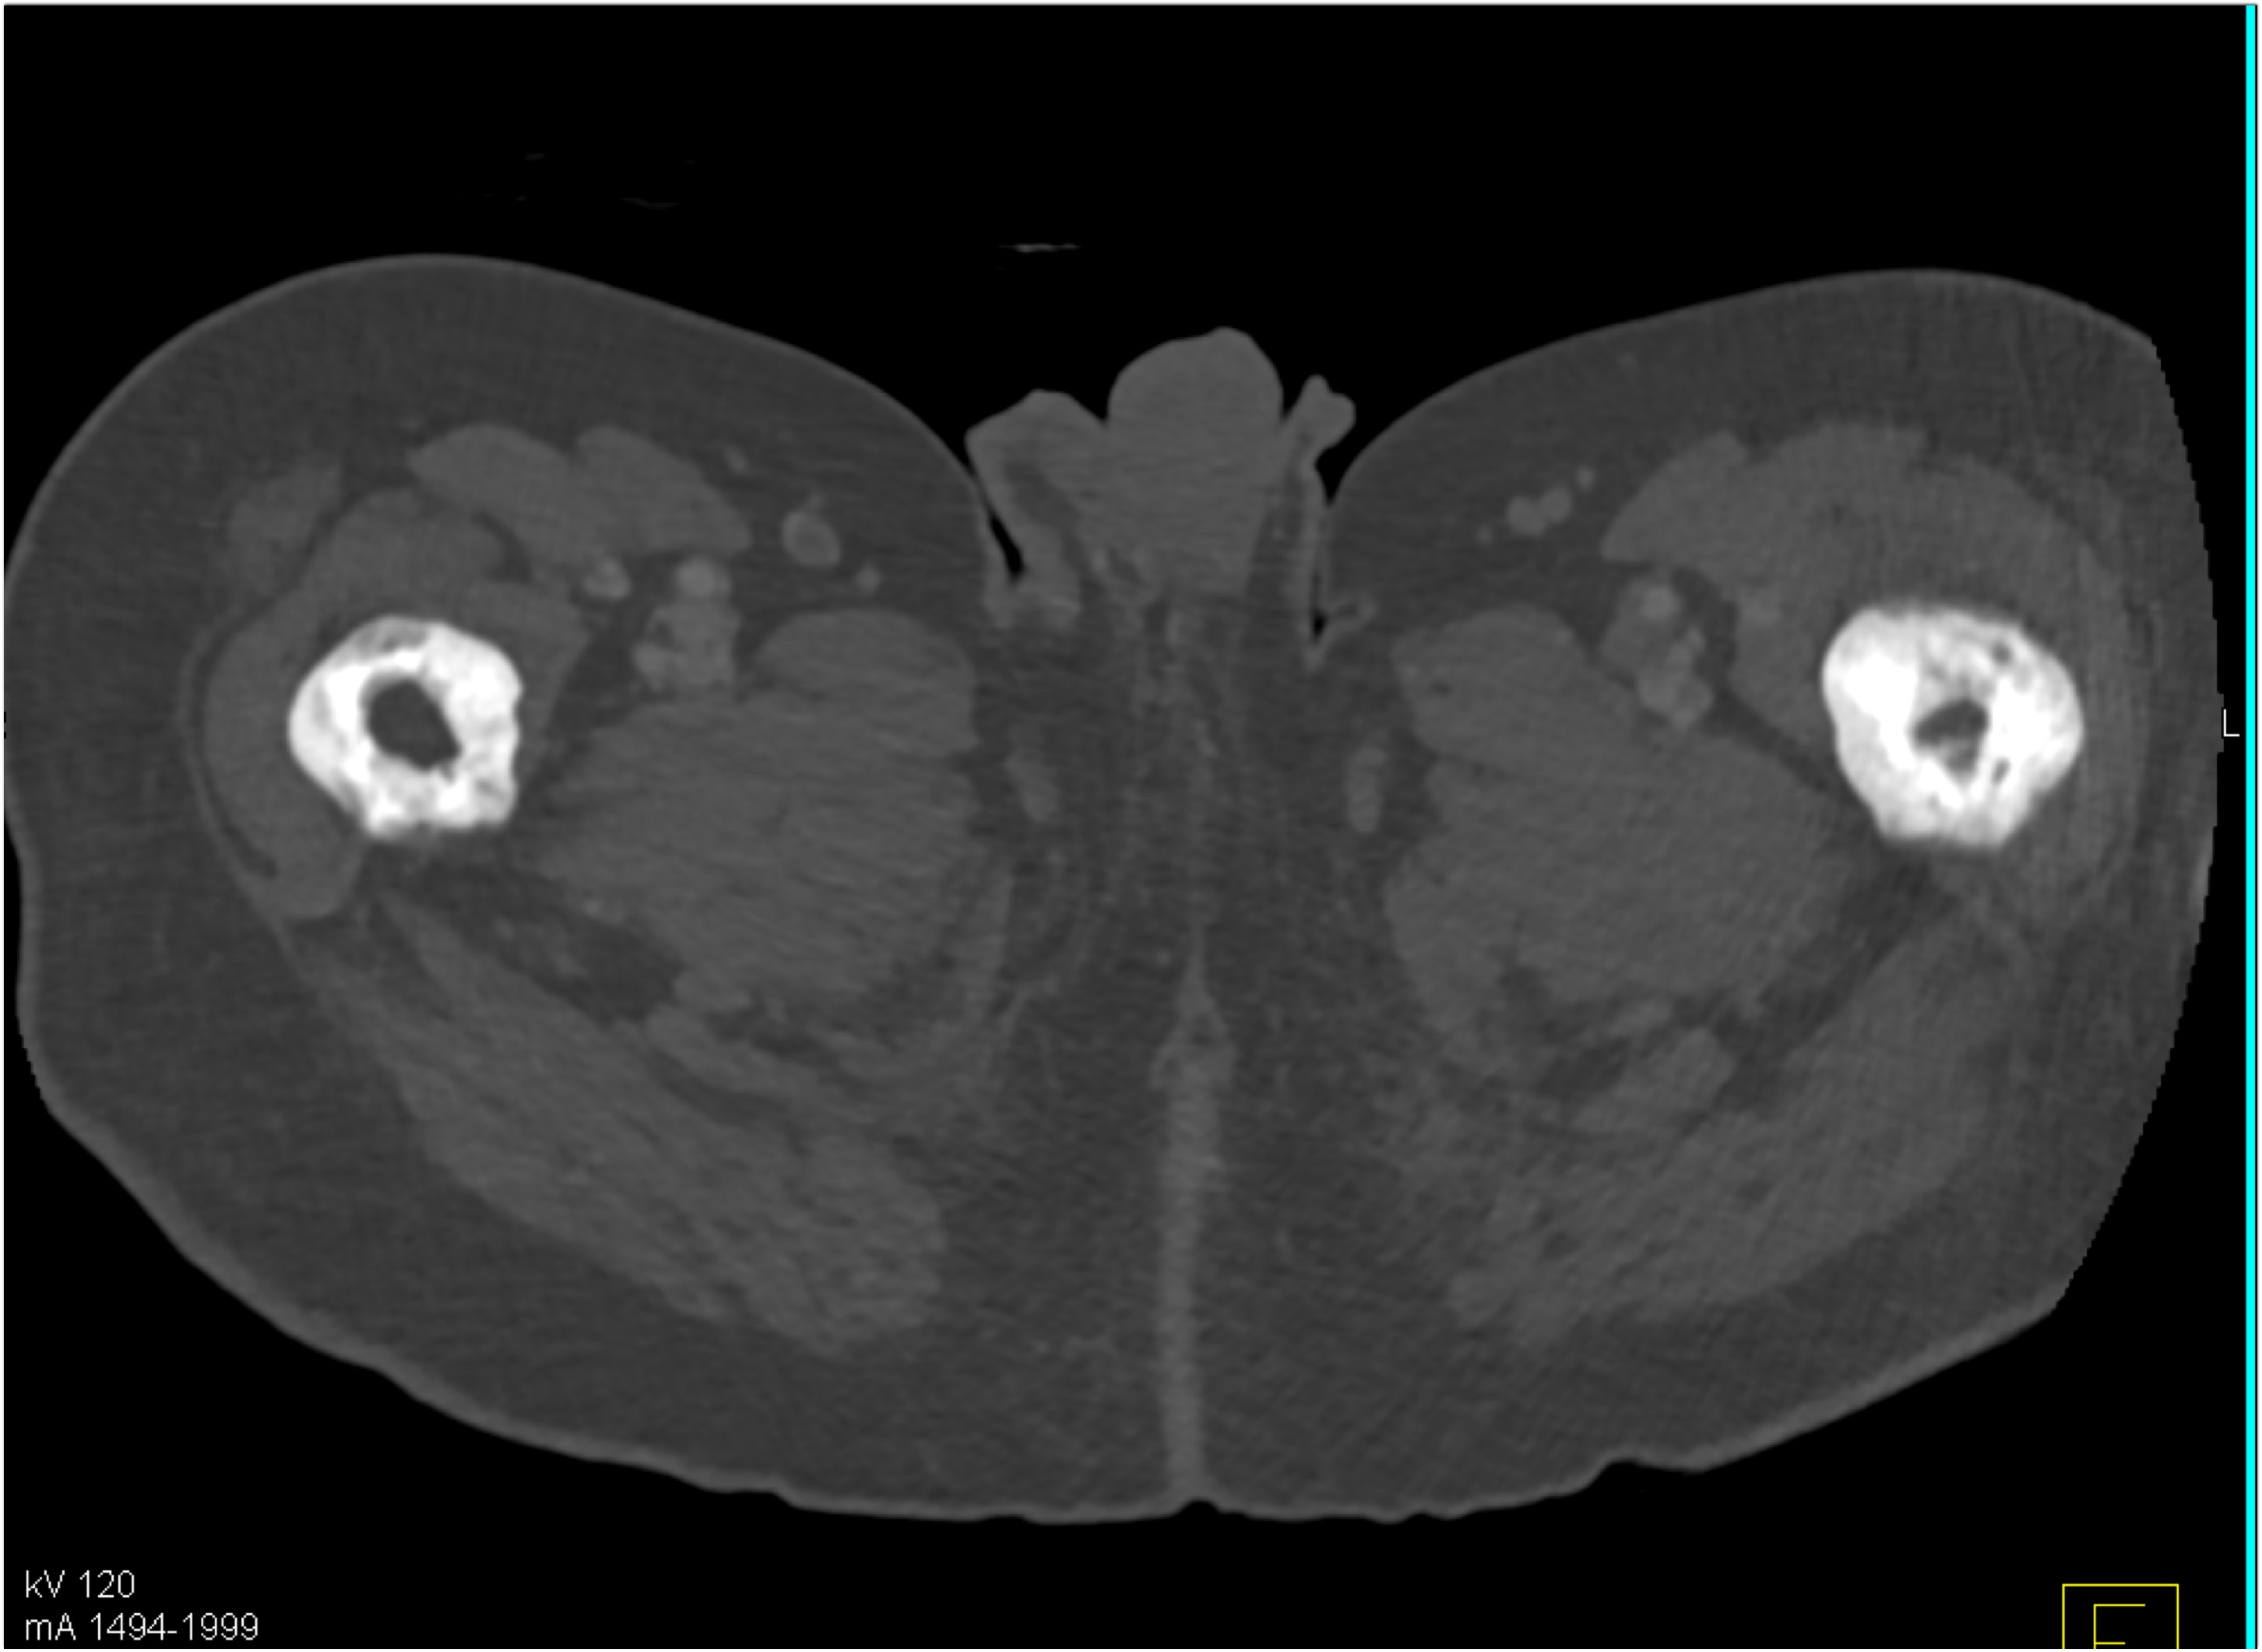

- Review your answers below.

4) The mass in the right lower lung in this patient post trauma is

pulmonary contusion

lung infarct

adenocarcinoma

pulmonary laceration